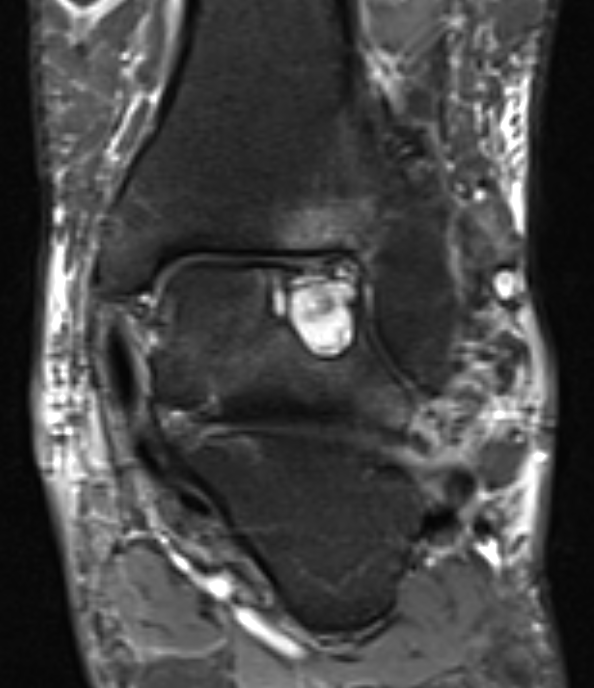

GCT flexor tendon sheath

GCT of tibialis posterior tendon sheath